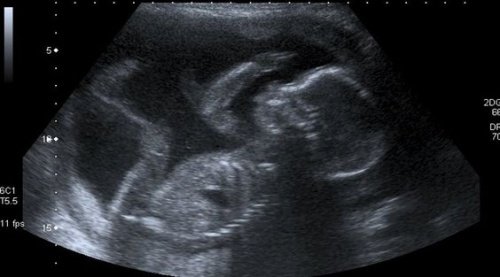

I de næste 9 måneder er hun nødt til at klare sig med uklare scanningsbilleder på en sort-hvid-skærm, før hun kan se sin søn eller datter ansigt til ansigt og opdage hudfarven, hårfarven og øjenfarven.